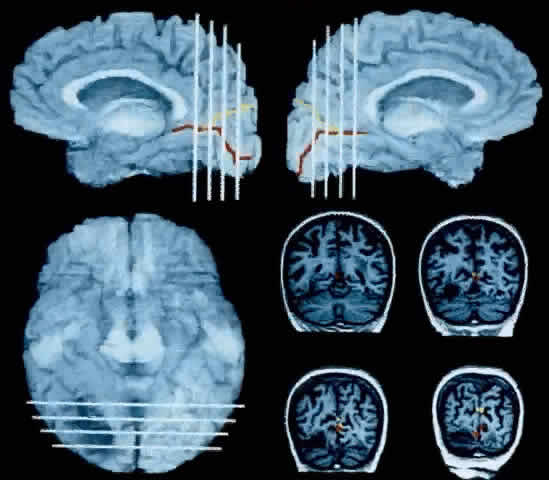

ANATOMY AND PATHOLOGY. The typical lesion in prosopagnosic cases lies in the inferior occipitotemporal cortex, in the fusiform and lingual gyri (Fig. 8).100,111,112 Opinion has varied as to whether prosopagnosia requires bilateral lesions. The early cases of Wilbrand (1892) and Heidenhain (1927) had bilateral damage.89 Reviews by Meadows112 and Damasio and colleagues100 stressed that all autopsies of prosopagnosic patients revealed bilateral lesions of the inferior occipitotemporal cortex; in some cases, the left-sided lesion was not suspected before the patient died.98,113 Other evidence for the requirement of bilateral lesions include studies of split-brain subjects showing mechanisms for facial recognition in both hemispheres and the lack of prosopagnosia in patients with right hemispherectomy89 (see Sergent and Villemure95 for an exception). Modern neuroimaging has also confirmed bilateral lesions in many cases with computerized tomography (CT),93,96,104,106,107 MRI,89,106 and positron-emission tomography (PET).114

Fig. 8. The brain of a 72-year-old woman with prosopagnosia, achromatopsia, alexia, and left homonymous hemianopia. The mesial surfaces of the right and left hemispheres, respectively, are reconstructed in the upper right and upper left panels from raw MRI data (Brainvox technique102). The ventral surface is in the lower left panel. The white lines through the reconstructed brain show the relative position of the four coronal slices shown in the lower right panel. The calcarine fissure and parieto-occipital fissure are traced in red and yellow, respectively, which automatically transfers to the coronal MRI slices. The patient had bilateral lesions that affected the fusiform gyrus and undercut the most posterior segment of the lingual gyrus. The larger lesion in the right hemisphere affected the optic radiations, causing the equivalent of a V1 scotoma in the left visual hemifield. The lesion of the left hemisphere does not reach the surface of the brain. It lies beneath the calcarine fissure and can be only in the coronal sections. Such a lesion would cause damage in a possible human homologue of the monkey's area V4 complex or disrupt connections to and from such an area. (Rizzo M, Smith V, Pokorny J, Damasio AR: Color perception profiles in central achromatopsia. Neurology 43:995, 1993)